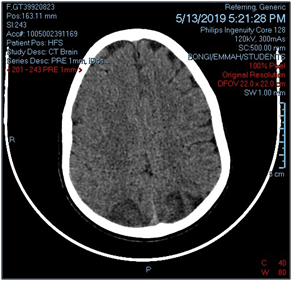

On day 3 post-operatively, she had single episode of generalised tonic-clonic seizures and she developed loss of vision. This was the first episode of seizure and loss of vision. Opthalmologist examination was normal. Computed Tomography(CT) brain revealed biparietal lobe hypodensities and associated mild surrounding edema with no mass effect. A diagnosis of PRES was made (Figure 1).

Figure 1 Biparietal lobe hypodensities and mild edema.